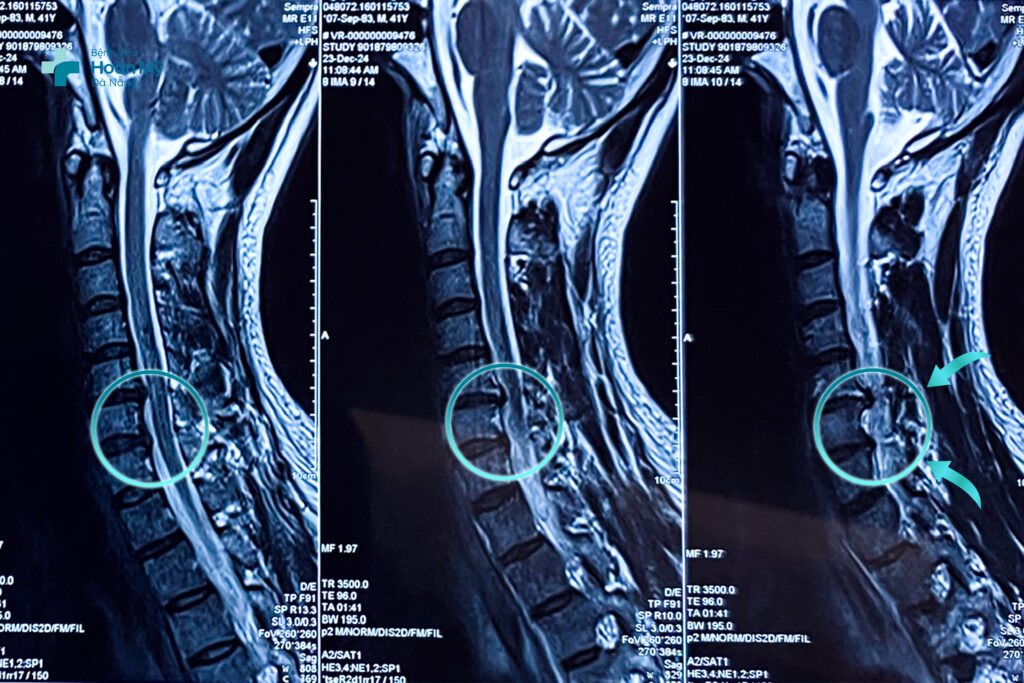

TS.BS. Lê Đình Huy Khanh – Trưởng khoa Ngoại Thần kinh – Cột sống, Bệnh viện Hoàn Mỹ Đà Nẵng chia sẻ: qua thăm khám, chụp MRI cột sống cổ có hình ảnh thoát vị đĩa đệm cổ C5-6 và C6-7 bên trái – phù tủy mức tương ứng. Người bệnh có chỉ định phẫu thuật ACDF (Anterior Cervical Dicsectomy and Fusion) lấy nhân thoát vị đĩa đệm và hàn xương cột sống cổ lối trước dưới sự hỗ trợ của kính vi phẫu, màn hình tăng sáng trong phẫu thuật, máy mài cao tốc nhằm giải phóng đĩa đệm chèn ép tủy cổ, rễ thần kinh cột sống, nhằm tránh nguy cơ liệt tay trái và cải thiện chất lượng cuộc sống.

Thoát vị đĩa đệm cột sống cổ hiển thị rõ trên MRI